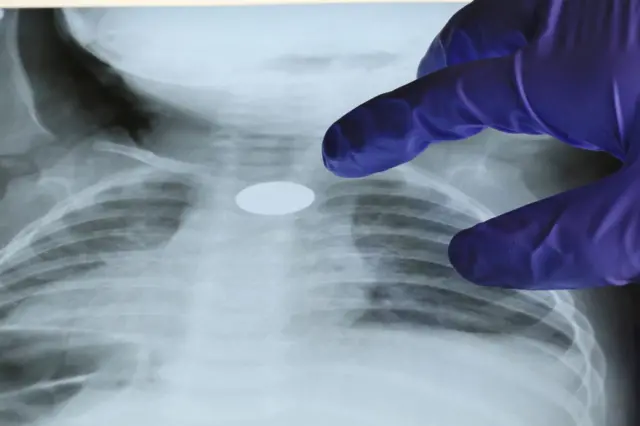

Fuente de la imagen, Getty Images

Tristemente, el lugar que estos objetos encuentran en el tracto respiratorio es una de las causas más comunes en la mortalidad de niños menores de 3 años.

Los niños tienden a meterse cosas en la boca, nariz y oídos. Las cosas en la boca y la nariz típicamente son inhaladas y se atascan en el tracto respiratorio, produciendo generalmente un reflejo por ahogamiento que expele el objeto.

Las cosas que los niños suelen inhalar van desde lo más conocido (juguetes, cuentas de un collar, imanes) hasta lo más inesperado (sanguijuelas y alfileres). Los objetos inhalados varían según la región.

En países occidentales, son los maníes los que más se inhalan, y las salchichas de los perros calientes las que provocan la mayoría de las muertes.

En el Sureste Asiático y China son huesos y semillas. La mayoría de los casos ocurren alrededor del año nuevo lunar. Y en países de Medio Oriente, África y el Mediterráneo suelen ser nueces o semillas.